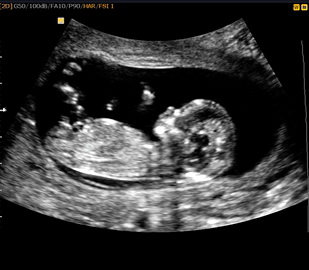

А тут нам уже 12 недель

Сердечко бьется все в порядке мама с папой